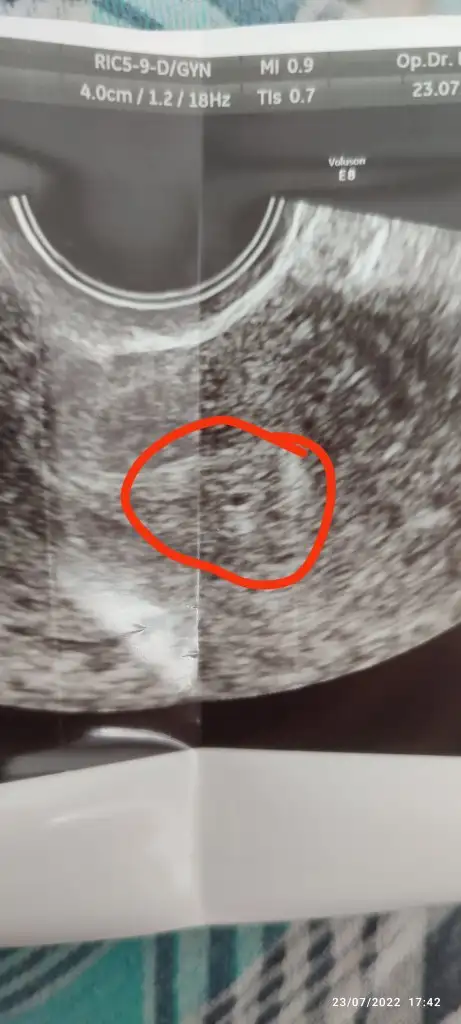

Bu cumartesi günü yapılan ultrasonda doktor bu bölgenin rahme yerleşmiş bir kese olduğunu söyledi bilemiyorum gerçekten kafam çok karışık